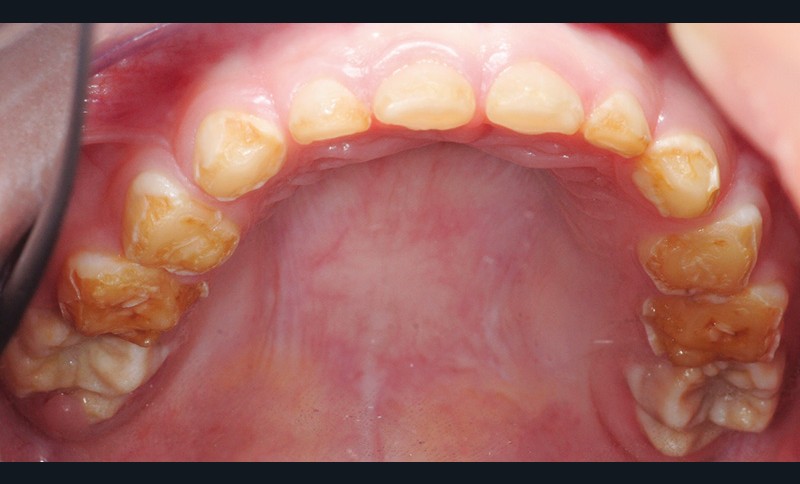

Quel est le principal diagnostic différentiel ?

(fig. 2 et 3)

Il s’agit de l’amélogénèse imparfaite héréditaire, qui :

• touche toutes les dents de l’arcade ;

• entraîne une coloration jaune orangée de l’émail sur toute la surface coronaire ;

• est liée à une étiologie génétique.